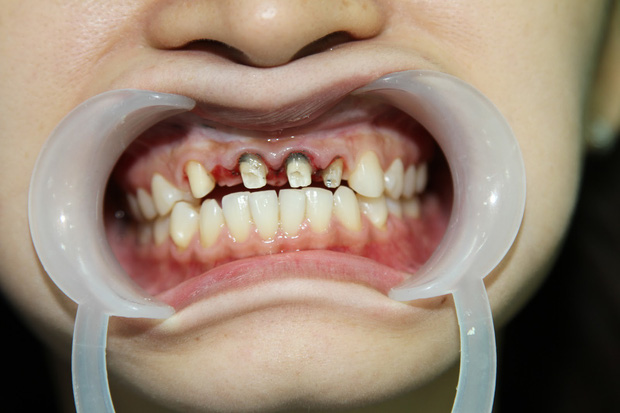

- Tụt lợi và lộ chân răng: Do phản ứng viêm kéo dài hoặc phục hình sai kỹ thuật, nướu rút lên làm lộ phần cổ răng hoặc sứ, gây mất thẩm mỹ và ê buốt.

- Viêm tủy, chết tủy: Việc mài răng quá mức hoặc không kiểm soát sẽ làm tổn thương đến phần tủy bên trong, gây đau nhức, nhiễm trùng, thậm chí mất răng vĩnh viễn.

- Viền sứ đen xỉn, lộ kim loại – đặc biệt là với dòng sứ kim loại rẻ tiền, gây mất thẩm mỹ nghiêm trọng.